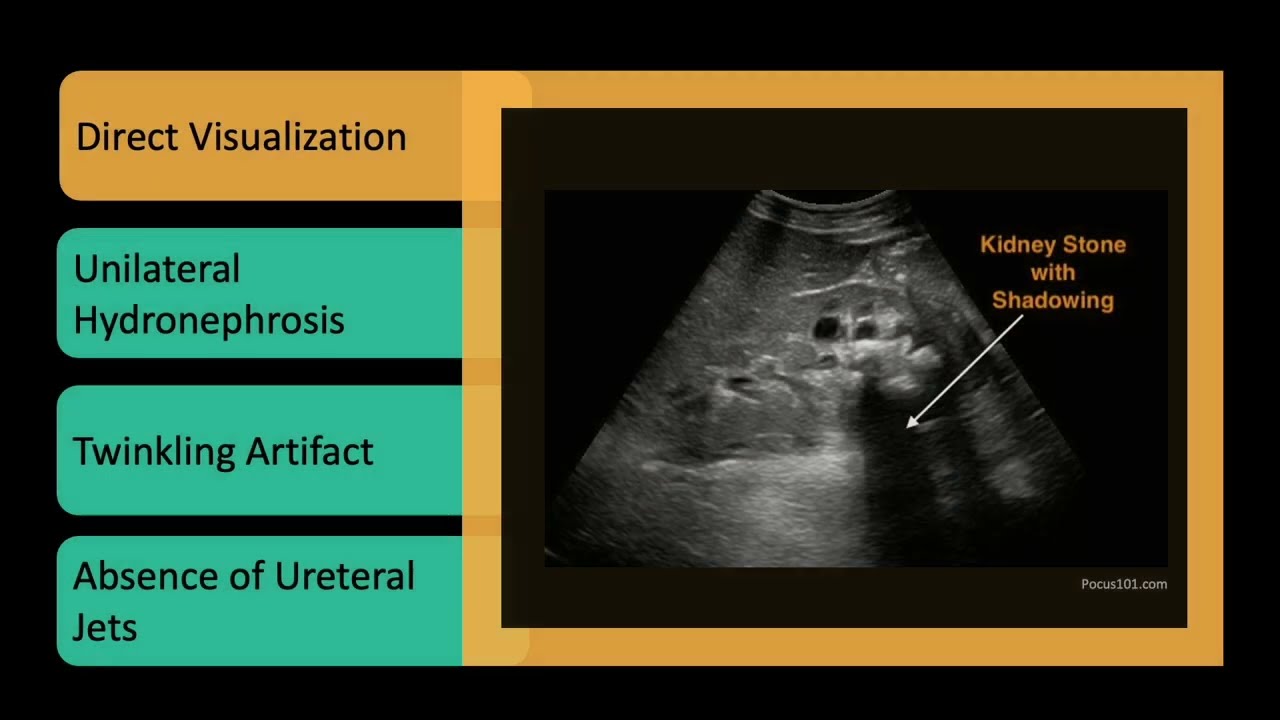

🪨 Clues for ureteral obstruction and when to suspect kidney stones

Keywords: Renal POCUS, Bladder Ultrasound, Hydronephrosis, Kidney Stones, Urinary Retention, Bedside Renal Scan, Family Medicine Ultrasound, Emergency POCUS, Urologic Imaging